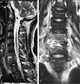

Pyogenic fibrositis

Localized soft-tissue calcification